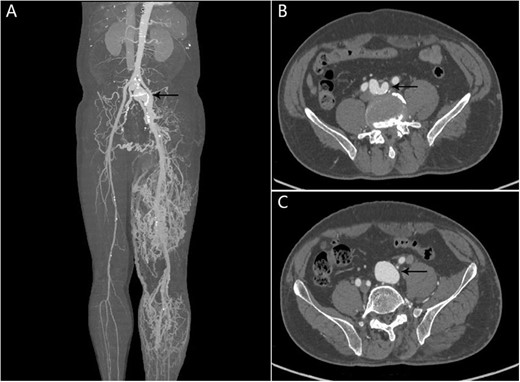

He had multiple hospital admissions with left lower limb edema and heart failure. He was diagnosed with deep vein thrombosis and pulmonary hypertension in the local hospital. On admission, clinical examination revealed bilateral basal rales in the lungs and abdominal bruit. The blood biochemical indexes were NT-proBNP 1075 pg/ml, and other biochemical indexes were within the normal range. Echocardiography demonstrated showed a severely dilated right ventricle. Chest X-ray revealed lung infection and pulmonary hypertension. Computed tomography angiography (CTA) showed there was an AVF between the right internal iliac artery and the left common iliac vein and dilated tortuous veins in the left lower limb (Fig. 1).

CTA showing AVF between the right internal iliac artery and the left common iliac vein. (A) The left common iliac vein and dilated tortuous veins in the left lower limb; (B, C) An AVF (black arrow) between the right internal iliac artery and the left common iliac vein.